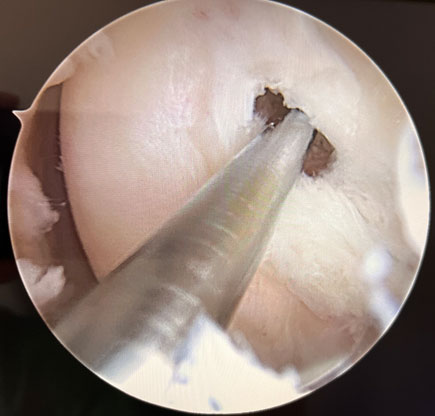

Arthroscopic femoral tunnel drilling

Tibial tunel drilling thanks to a custom made guide arthroscopically assisted

Tibial tunel drilling thanks to a custom-made guide arthroscopically assisted